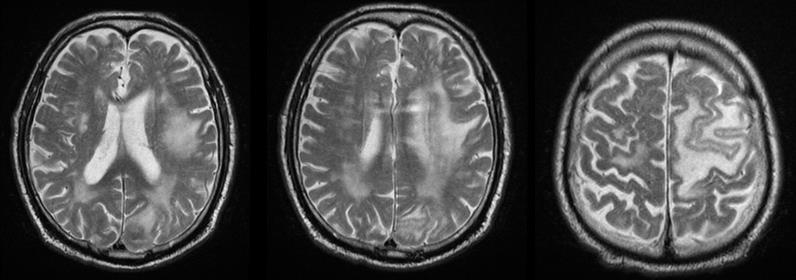

A 73-year-old patient after fibrobronchoscopy (FBS) with histologically and immunohistochemically (IHС) proven small cell lung cancer (SCLC) (T4 N1 M1/pleural) was presented. First-line chemotherapy (Ch) (Cisplatin and Etoposide) were performed. CT of the lung after 6 cycles of Ch - Tumor lesion of the right lobe bronchus with infiltration of the pleura - without dynamics. No secondary changes are reported bilaterally. Mediastinum - without enlarged lymph nodes bilaterally. A small discrete effusion in the right pleura was reported. CT of the brain - No secondary changes in the brain parenchyma. Ventricular system - unexpanded (Figure 1).

Three months after WBRT, the patient complained of difficulty in balance and weakness of the right limbs. CT of brain with venous contrast - Parenchymal brain pathology is not visualized subtentorially. Edema zones temporoparietally and occipitally in the left cerebellar hemisphere, without visible nuclei of metastases are reported. Ventricular system and basal cisterns - undilated, without dislocation. Mild cortical atrophy bilaterally temporally is visualized (Figure 3).

Figure 3: CT of the brain after 3 months of prophylactic WBRT - Edematous areas temporoparietally and occipitally in the left cerebral hemisphere.

MRI of the brain (Figure 4) - Against the background of advanced changes in chronic ischemic disease of the small vessels, in the left parietal extensive cerebral edema, mild compression of the body of the left lateral ventricle. Post-contrast scans lack pathological capture of the contrast material. Infratentorial without evidence of pathological lesions. Conclusion - The MR finding corresponds to subacute changes after RT, without data on the presence of radionecrosis and without data on metastases. The patient was hospitalized with a worsened general condition and complained of fatigue, dizziness, hemiparesis of the right limbs and central involvement of the right facial nerve. Despite anti-edema and antiinflammatory therapy, the patient exits after 18 days.

The whole-brain radiotherapy (WBRT) is conducted for two therapeutic purposes - preventive or prophylactic and curative. PWBRT is a standard approach in the limited or advanced stage of small cell lung cancer (SCLC) in clinical remission after systemic chemotherapy (Ch) and local pulmonary radiotherapy (RT). Without PWBRT, 60% of SCLCs develop brain metastases (BM), and they are reduced to 20% after it was performed [10]. PWBRT is also recommended for non- small cell lung cancer (NSCLC) [11-15], in which a significant reduction in BM of 18% to 8% without improved overall survival (OS) has been achieved [16] in contrast to SCLC, where OS is significantly increased [17,18]. The purpose of PWBRT is to destroy microscopic metastatic tumor cells in the brain before their clinical manifestation. Radiation brain effects after PWBRT are divided into acute, subacute and chronic [19]. Acute side effects occur during or one to two weeks after completion of PWBRT. They are expressed by general fatigue, alopecia and symptoms associated with increased cerebral edema - headache, nausea, focal brain deficits, a pronounced mental change [20]. These acute symptoms gradually subside in a large proportion of patients. On MRI, diffuse cerebral edema is visualized [21]. Subacute symptoms develop immediately after the completion of RT or three months after its completion. They are relatively rare and limited, mainly to drowsiness syndrome and less commonly as leukoencephalopathy [20]. 3 months after 10x3Gy PWBRT, the condition of a 73-yearold SCLC patient, who underwent 6 courses of Ch (Cisplatin and Etoposide) deteriorated. CT and MRI visualize extensive cerebral edema in the left hemisphere, without brain metastases (Figure 3 & 4). In children with leukemia after PWBRT, there is a “radiation somnolence syndrome” characterized by somnolence often associated with headache, nausea, vomiting and sometimes fever. The necessary treatment is the administration of corticosteroids, but it should be noted that these complaints may resolve spontaneously [22]. Somnolence is more common in children with PWBRT with concomitant chemotherapy (methotrexate/ intrathecal) [23]. Pathophysiologically, this somnolent syndrome is associated with transient demyelination of the white matter. On the other hand, it should be noted that leukoencephalopathy is considered a more severe manifestation of demyelination and may be fatal. These changes in white matter are much more common in adult patients with concomitant chronic cerebrovascular ischemia [20]. Symptoms are usually mild and stabilize or resolve. Imaging - CT and MRI with intravenous contrast varies from diffuse cerebral edema to increased accumulation of contrast [21]. In the presented adult patient it can be seen that against the background of antiedema medication treatment (Dexamethasone and Mannitol), the symptoms was not transient, on the contrary, they worsen (Figure 3 & 4). Subacute encephalopathy usually begins two or three months after cerebral RT but may occur 2 weeks to 4 months after completion of PWBRT. It is usually seen in patients with SCLC after chemotherapy of the primary tumor. The pathogenesis of subacute encephalopathy is due to demyelination due to damage to the oligodendroglia with subsequent involvement of the myelin sheaths [22]. The progression of these changes leads to late effects manifested by radionecrosis [23-25]. Tissue necrosis is a distinct syndrome of radiation toxicity, thought to be the consequence of vascular endothelial cell damage, resulting in fibrinoid necrosis of small vessels and direct brain parenchymal necrosis. Occlusion of small blood vessels results in focal coagulative necrosis, capillary leakage, and demyelination of the surrounding brain parenchyma [26,27]. The relationship between PWBRT and late brain toxicity was analyzed in 264 patients with limited stage SCLC [28]. Patients are divided into 3 arms depending on the DD and the TD: 10 fractions up to TD 25 Gy; 18 fractions up to TD 36 Gy and hyperfractionated RT ( two daily fractions) with 24 fractions up to TD 36 Gy. Neurological changes are reported after 6 months and 12 months of PWBRT. After 1 year, neurotoxicity was established in 60% of patients after TD 25 Gy and in 80-90% after TDs 36 Gy.